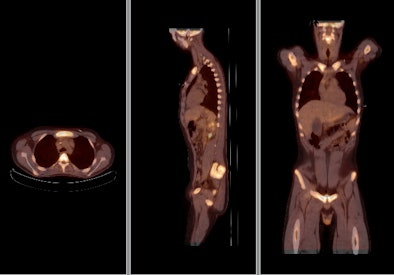

![]() |

| FDG-PET/CT with integrated contrast CT shows a large tumor in the left lung with hilar lymph node metastases. Image courtesy of Siemens Healthcare and the University of Minnesota. |